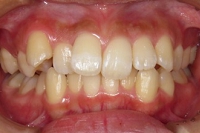

CASE2

↓前歯の歯並びを きれいに治したい。

(35歳/女性)

概要・担当医コメント:叢生・審美障害↑

動的治療期間13ヶ月(12回)/非抜歯/費用概算:55万円

上は固定式のブラケット矯正で,下は患者様ご自身が着脱するマウスピース矯正の治療を行いました.治療結果には大変満足されているそうです.